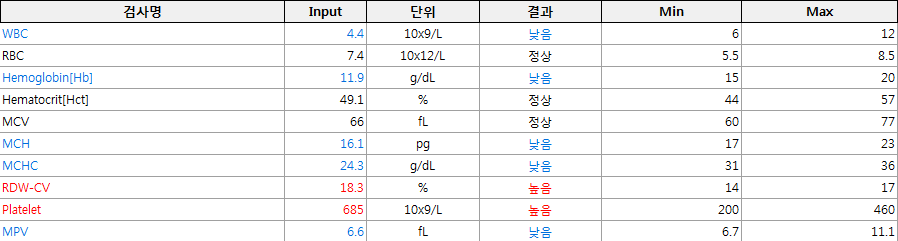

마취의 위험을 줄이기 위해 꼼꼼한 검사와 수액처치 후 호흡마취로 수술에 들어갑니다.

자궁축농증의 점과 어린이의 나이를 고려하여 혈액 검사 결과를 체크하고, 신중하게 마취를 하여 수술을 마쳤습니다.

자궁 내의 고름 때문에 자궁이 팽창하고 있고, 체내의 염증치도 꽤 높은 상태입니다.

자궁과 난소를 완전히 적출하는 수술 후 상태가 안정되면 며칠 내에 수치가 안정됩니다.

이는 검사상의 수치와 식욕 증가 및 활력의 정상화 등 전반적인 상태의 호전에서도 확인할 수 있습니다.